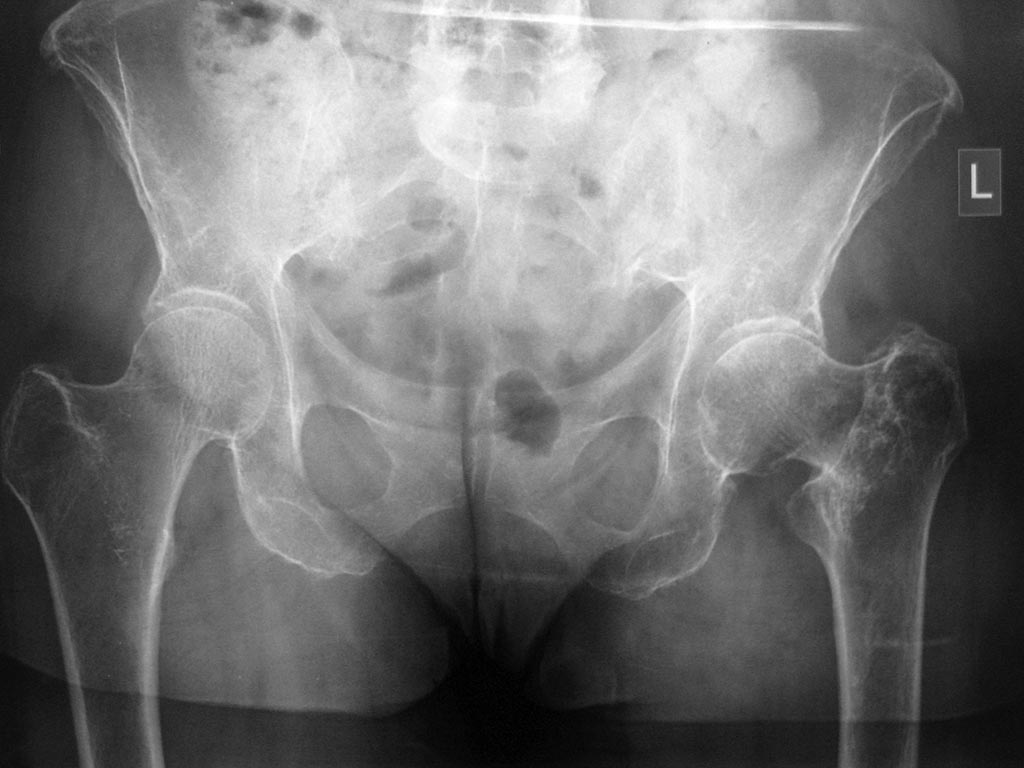

Обратилась женщина, 66 лет, лечится стационарно в неврологическом отделении

по поводу болей в поясничном отделе позвоночника. В декабре получила

чрезвертельный перелом левого бедра(упала), лечилась консервативно. В

настоящее время ходит с умеренной хромотой, движения в левом

тазобедренном суставе свободные, практически безболезненные.

Укорочение конечности 2-3 см. Сама больная появление болей в

позвоночнике связывает с укорочением конечности. При КТ позвоночника

выявлена компрессия L2 на фоне остеопороза.

Обратилась на консультацию с требованием коррекции длины конечности.

1.Целесообразно ли оперативное лечение в данном случае или

достаточно коррекции ортопедической обувью

2.Если оперативное лечение,то корригирующая

остеотомия или протезирование (учитывая возраст и наличие коксартроза на

рентгенограммах)